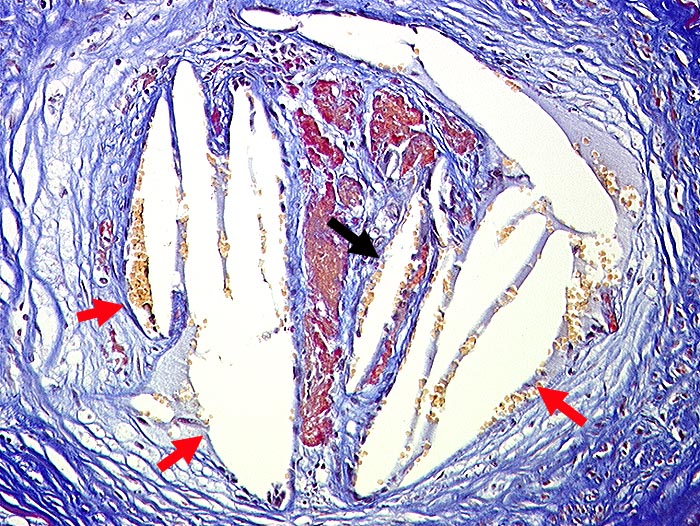

Cholesterinembolien verschiedenen Alters

Durch die Fixation herausgelöste Cholesterinkristalle sind als wetzsteinförmige Hohlräume im Gefässlumen sichtbar. Eine ältere Embolie ist umgeben von Bindegewebe.

Cholesterinemboliesyndrom bei schwerer allgemeiner Atherosklerose. Nachweis unterschiedlich alter Cholesterinembolien in Nieren, Milz, Magen, Darm, Pankreas, Haut und Muskulatur. Infarkte von Nieren und Milz. Hautnekrosen.